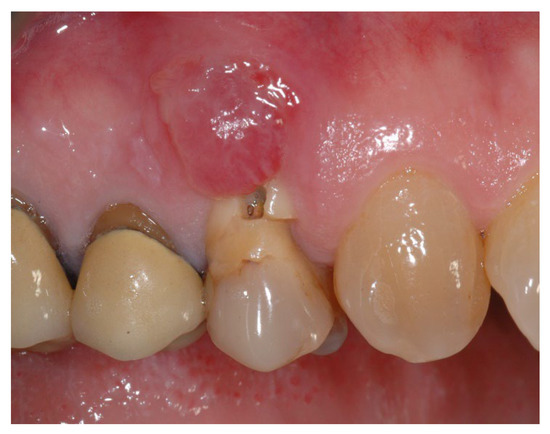

2.2. Clinical Procedures